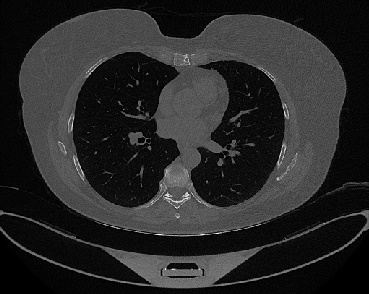

It should be mentioned that for explainability purposes [7, 8, 9], an anchor set was generated for the COV19-CT-DB database [5]. This included 11 anchors, each representing a respective 3-D CT scan obtained through an appropriate clustering procedure. Figure 2 shows a series of slices from a COVID-19 case, whereas Figure 3 shows a series of slices from a non COVID-19 case.